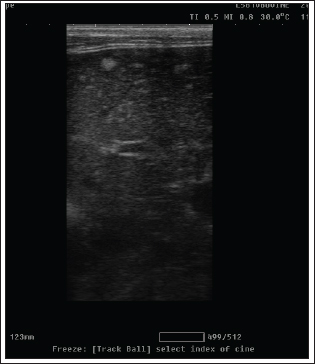

Ultrasonography

On ultrasound images, mammary gland tissue showed higher echogenicity than normal tissue. The FMH lesions were well-defined, slightly hyperechoic, lobulated masses containing multiple small anechoic clefts within the mammary parenchyma.

The intraductal pattern is dominant, with anechoic areas corresponding to clefts of different shapes within the mammary gland parenchyma. The presence of clefts in mammary fibroepithelial lesions provided a more heterogeneous appearance to the ultrasound images (Fig. 4). In the solid lesions, the ultrasound pattern is more homogeneous (Fig. 5).

Fig. 4. Ultrasonographic image of lesions presenting cleft-like anechoic areas and characteristics of the intraductal pattern.

Radiology was of little interest in cases of FMH, as lateral abdominal surveys only reveal the enlargement of the mammary glands with an intact body wall (Burstyn, 2010). In comparison, ultrasonography provides more valuable information about the assessment of lesion pattern and echogenicity. Similar findings have been reported (Payan, 2013). In the present study, medical treatment was administered to 25 cats using cabergoline drug administration (5 µg/kg once daily PO), which proved effective in the majority of treated cats, leading to substantial regression of mammary size within three to 6 weeks, as previously reported (Giménez et al., 2010; Akkuş and Yaprakcı, 2024).